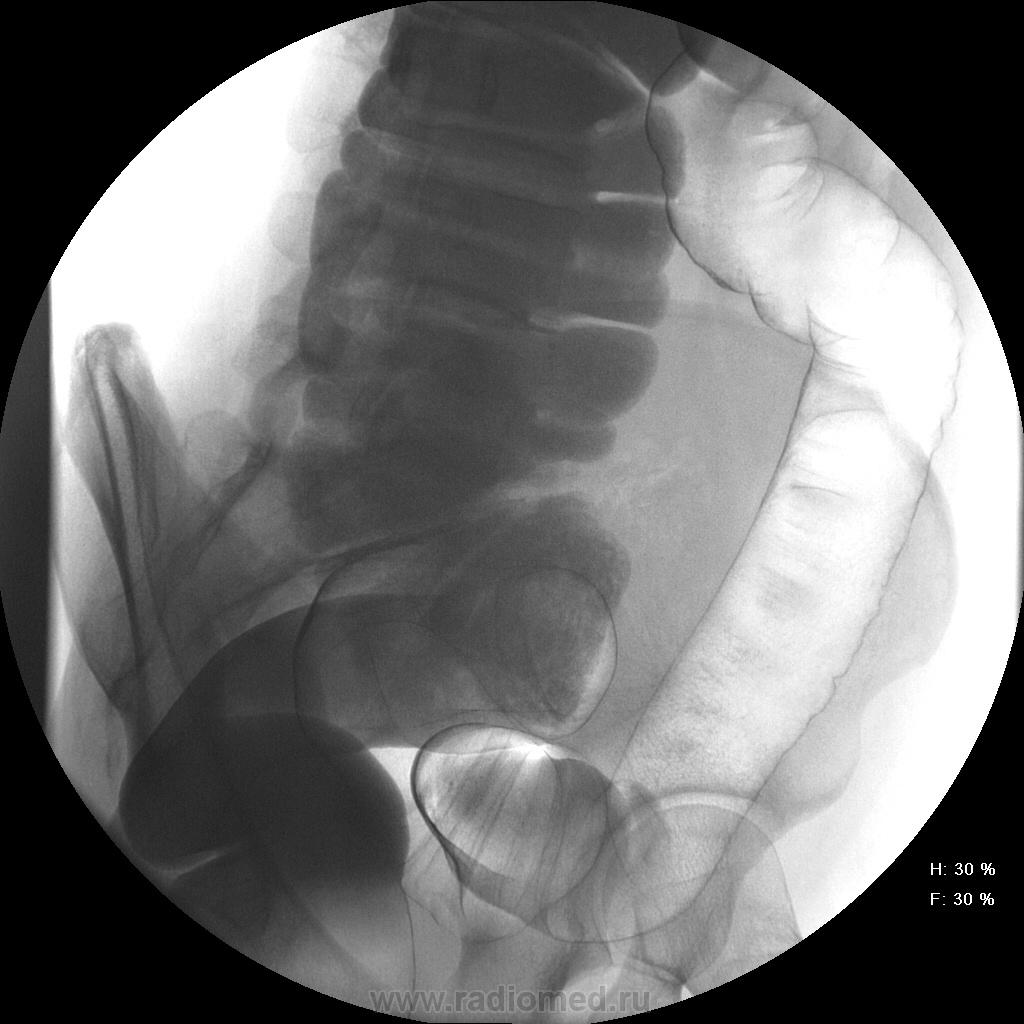

Девушка, 27 лет, жалуется на периодические боли в правой подвздошной области, области паха справа. Во время этого идет нарушение стула - то слабит, то несколько дней не может ходить в туалет, вздутие кишечника. Жалобы несколько лет . Обследованна кем только можно. Хирург посоветовал ирригоскопию. Работа достаточно нервная. До первого случая данных проблем , за неделю, проходила сан лечение в пансионате ( для поднятия общего иммунитета - так говорит), был курс клизм с травами - сама думает, что это не связанно.

А, чем вызвана неоднородность контрастирования слепой и частично восходящего отдела?

Тугого контрастирования слепой не достигнуто. Должны быть причины.

Слепая кишка в конце исследования, несмотря на её содержимое, заполнилась прилично. А вот гаустрация сигмовидной кишки не сглажена?

Признак долихосигмы - это наличие т.н. симптома "трехстволки", есть это - есть и долихосигма. В данном случае такой вариант имеет место быть.

Не буду уточнять конкретно, ну уж очень близкий человек на курорте попался на такую же удочку (повышение иммунитета), и после этого такие же жалобы, боли...На ирригуше написал норму, хотя проктолог на ней увидел колит. На колоноскопии - тоже колит, что-то назначали. но прошло само собой. И первопричина, я думаю, эти орошения. Попытаюсь сейчас найти снимки, сфоткать (как получится). Короче на фоне окна тюли и улицы...Да, это было в 2001 году. До сегодняшнего дня - жалоб нет. А на представленных снимках я бы никчему бы не придрался.